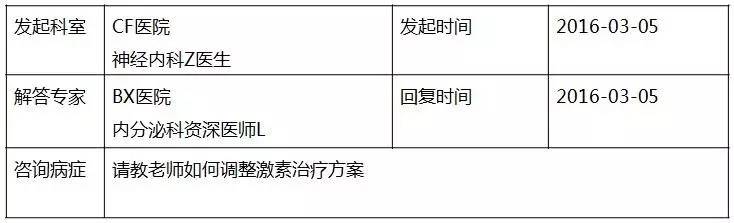

患者:女,30岁,主因“停经33周,胎动减少10天、胎心监测反应差1天”入院。

▼患者病程记录资料